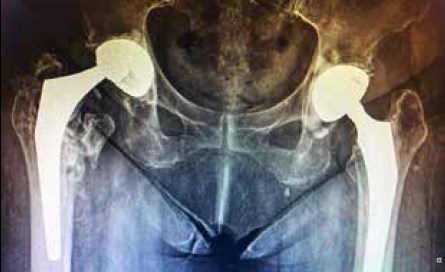

Con relación a las complicaciones no se detectaron infecciones, ni dehiscencias de herida, y como hallazgo no sintomático encontramos una luxación intraprotésica. La paciente en cuestión, de 81 años y en tratamiento por obesidad mórbida, consultó por traumatismo de la cadera contralateral secundario a caída de propia altura. Según el interrogatorio, desde la cirugía mantuvo un hábito de deambulación intradomiciliario negando cualquier dolor en la cadera con la copa tripolar (Figura1).

Figura 1. Marini. RX al ingreso del

paciente. Hallazgo incidental, luxación intraprotésica de cadera derecha.